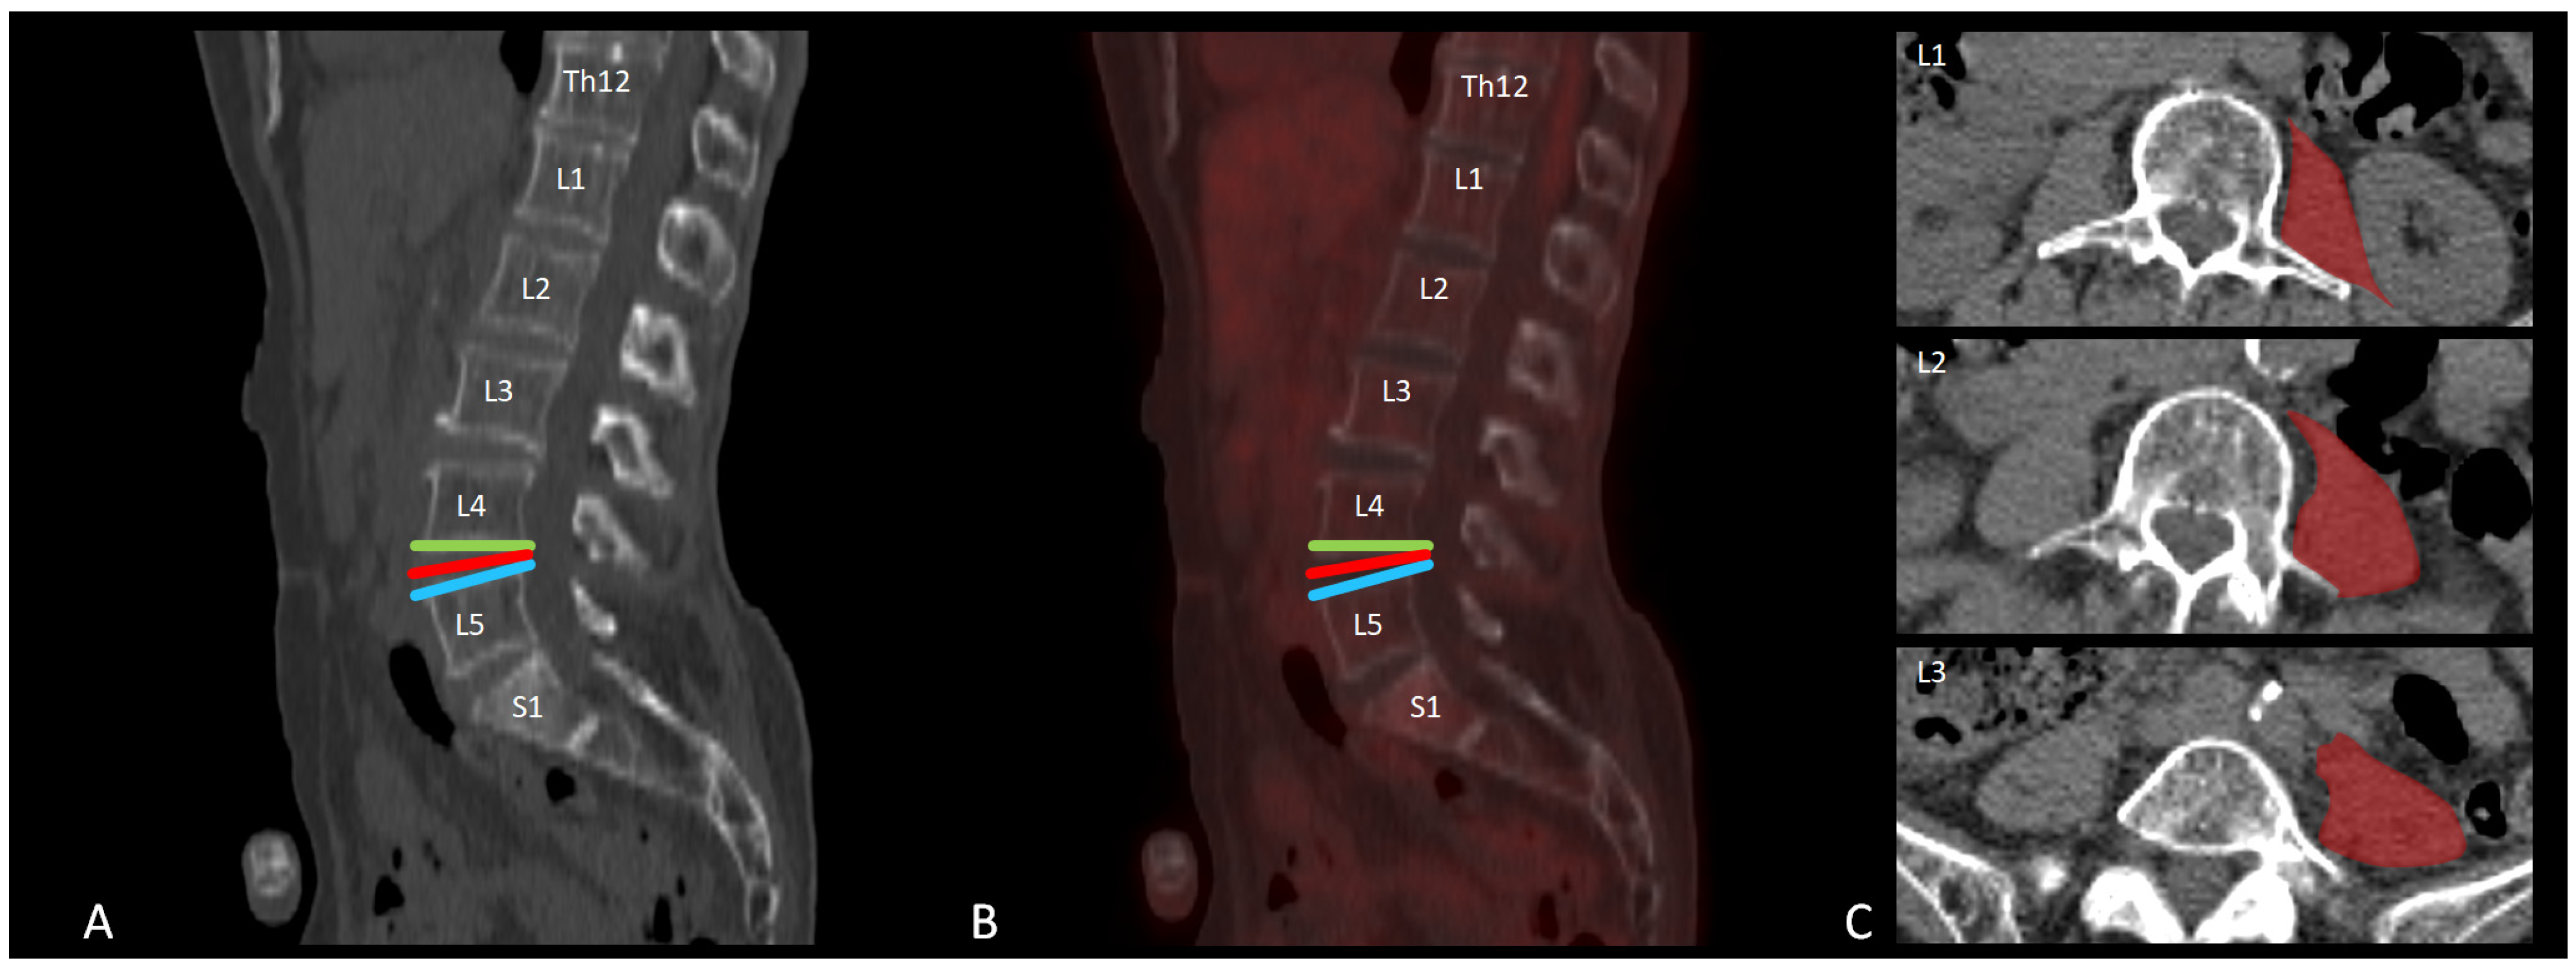

2.4. [18F]FDG PET-CT Data Analysis